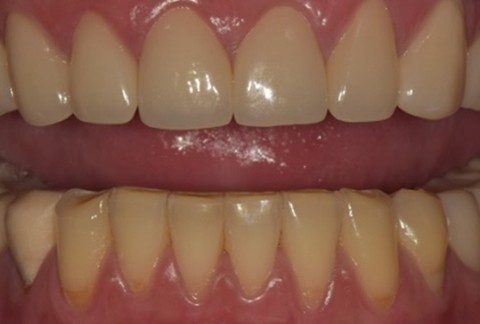

임플란트-전후사진